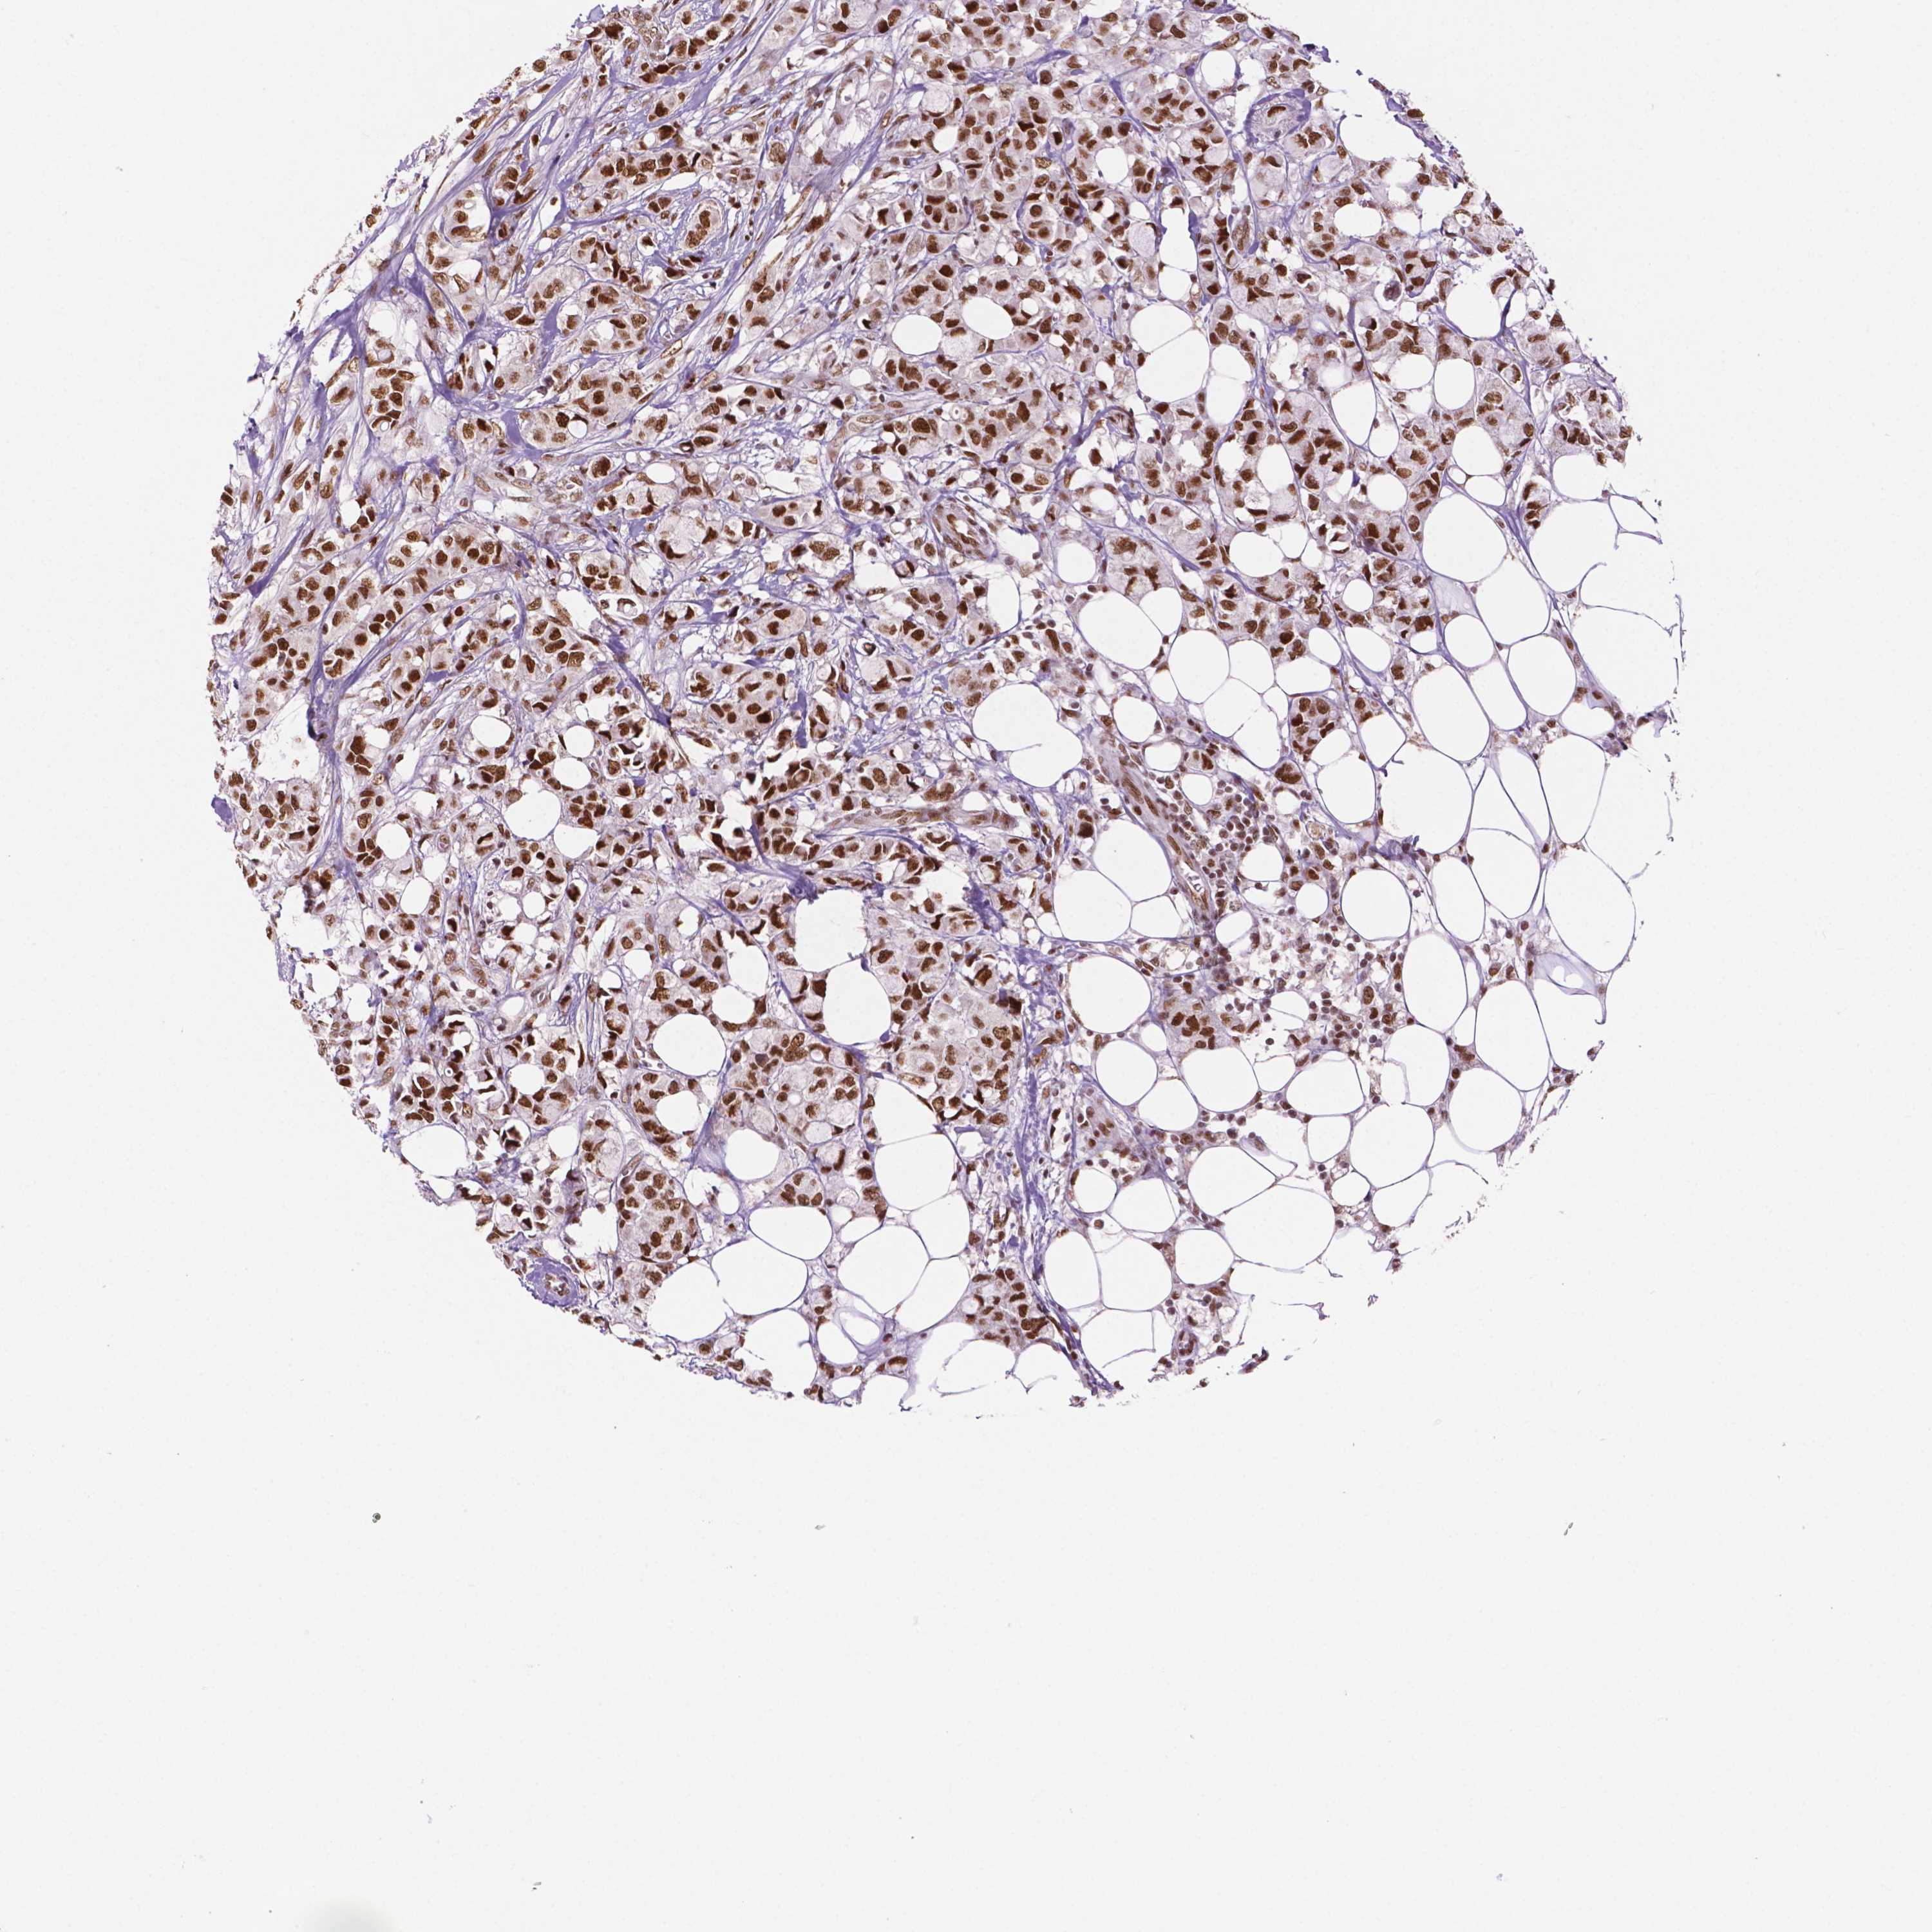

CANCER BREAST CANCER Show tissue menu

BRCA TCGA BRCA VALIDATION PROTEIN EXPRESSION